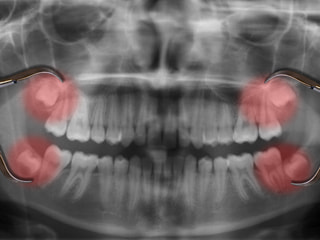

親知らずとは前歯から8番目に位置する歯のことで大きい歯の一番奥に生えてくる歯を言います。

生え始める年齢は早い方で15歳から、遅い方で20歳前後で生え始めます。 ななめに生えてくることや、半分埋まった状態で生えることもあり歯茎の腫れや痛みを引き起こす原因になります。

顎が小さい傾向にある現在の日本人は、顎の奥に親知らずの生える場所がなく、正しい位置にうまく生えないことが多くあります。そのため、前の方に傾いて生えたり、横向きに生えたり、歯の一部だけしか顔を出さない時もあります。

また親知らずは埋伏歯(まいふくし)といって、歯があるのに骨や歯肉の中に埋まったままで萌出しない場合があり、埋伏歯があると隣の歯に悪影響を与えたり、手前の歯が圧迫されて歯並びが乱れたりすることがあります。また埋伏歯と歯肉の隙間から細菌が侵入して化膿してしまうこともあるため、何らかの症状がみられる場合は、抜歯をすることがあります。